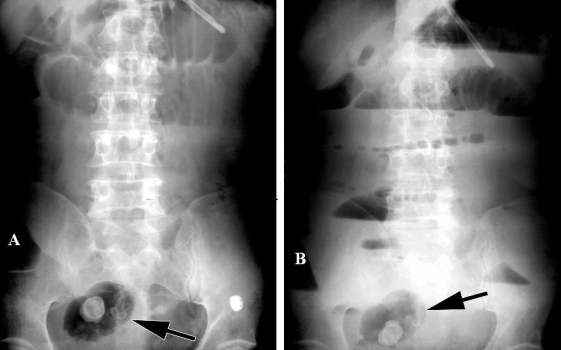

Hình 14: Tắc ruột non do xoắn túi thừa Meckel ở bệnh nhân nam 30 tuổi. A, x quang bụng nằm ngửa, B chụp bụng đứng. Một bóng khí hình oval chứa nhiều nốt vôi dạng viền bên trong ở ¼ bụng dưới phải (mũi tên). Sau phẫu thuật là túi thừa Meckel bị xoắn (Angela D. Levy, Christine M. Hobbs (2004). Meckel Diverticulum: Radiologic Features with Pathologic Correlation. RadioGraphics 24:578)